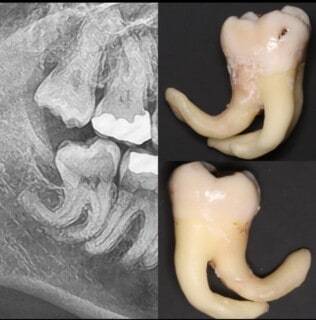

Crazy roots...

We can't get enough of amazing ORAL SURGERY! We accept referrals for complex extractions.. this one was a lovely challenge...